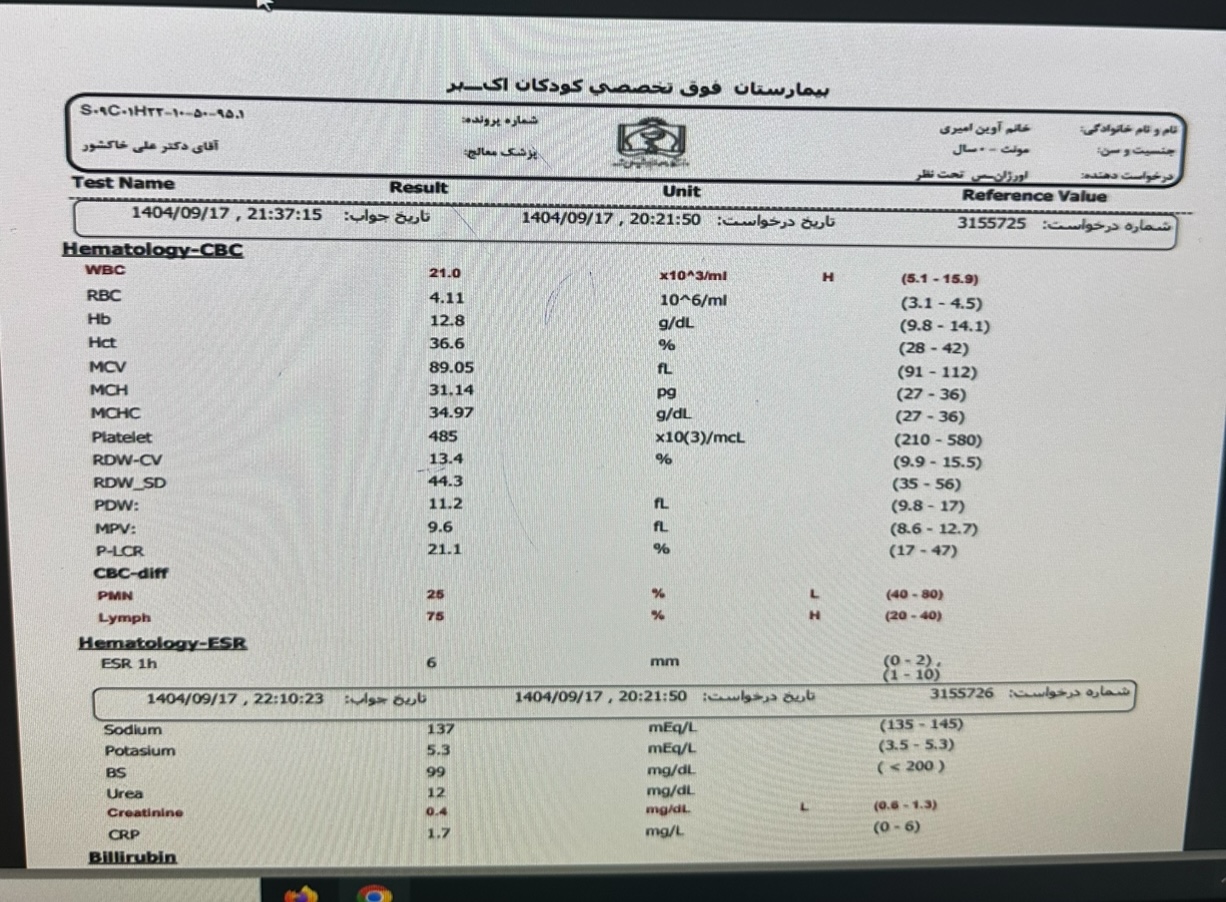

تو ازمایشات لنفوسیتوز

WBC=21000, lymph=78%

EsR,CRP=normal

Cbc